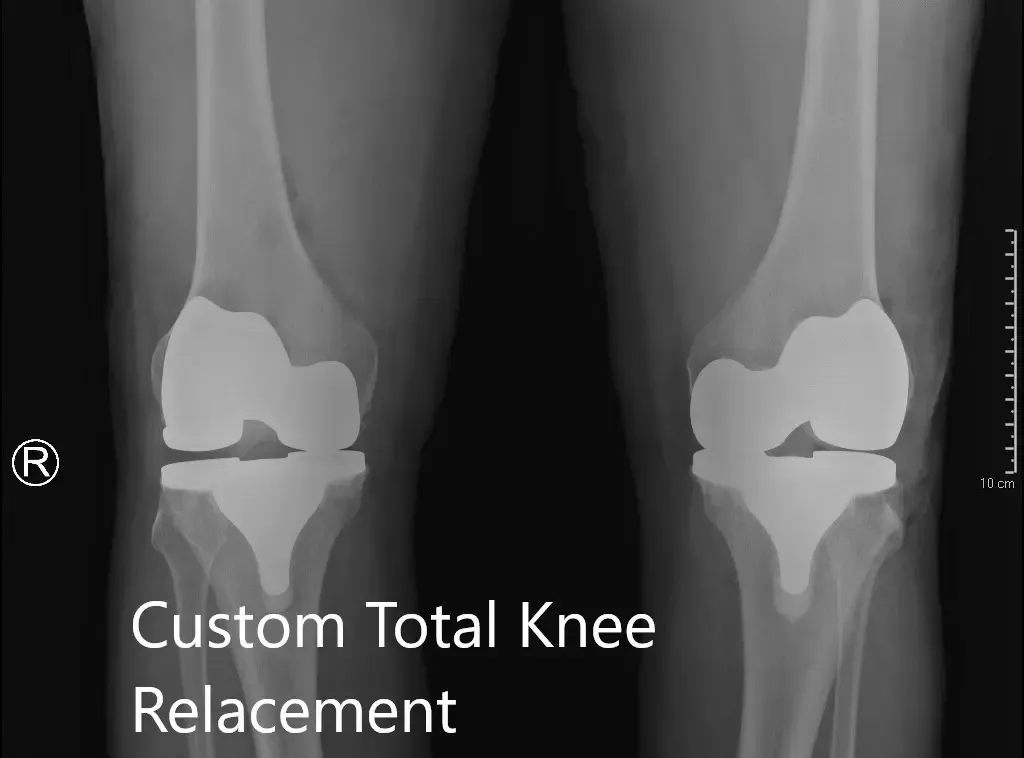

Postoperative X-ray showing the AP view of both knees.

IMPLANTS USED: Custom femoral implant with a tibial tray with 6-mm polyethylene inserts on the right side with 29-mm patellar component. Custom femoral implant with a custom tibial tray with 6-mm polyethylene inserts on the left side with the 32-mm patellar implant.